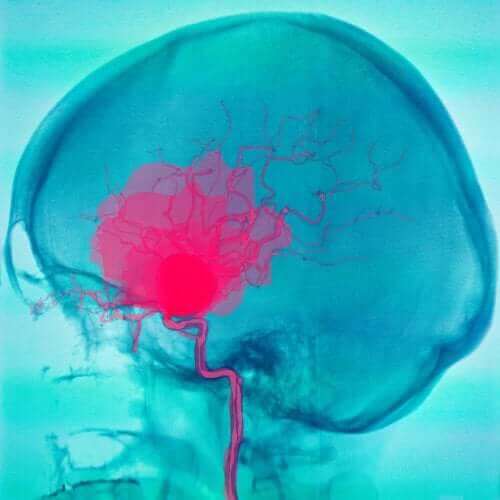

Субарахноидни и субдурални кръвоизливи

При субарахноидните и субдурални кръвоизливи първото нещо, което се наблюдава е изтичането на кръв от кръвоносните съдове. Тези съдове се намират в пространството между обвивките. Затова се уврежда мозъчната тъкан.

Субарахноидни кръвоизливи

Субарахноидните кръвоизливи са тези, при които кръвта изтича между паяжовидната и меката обвивки. Обикновено кръвта изтича от артериите и могат да се дължат на различни причини. Най-често срещаната е руптурата на аневризмата. Но този вид хематоми могат да се дължат и на други фактори.